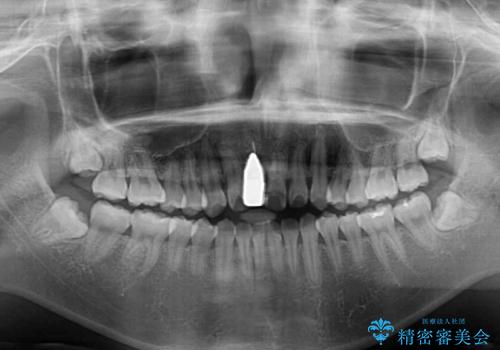

- 中学生の頃にぶつけた前歯に不格好なクラウンが装着されており、出っ歯な印象になっていることを気にして来院された患者様です。

ぶつけてしまった歯は保存が困難な状況であったので抜歯をし、ワイヤー矯正により歯列を整えつつ前歯の突出感を解消することとしました。

矯正治療後にはインプラント補綴治療を行うこととしました。

前歯の補綴治療はインプラントかブリッジかで悩んでいました。

周りの歯にむし歯がないため、インプラントがお勧めとなりますが、事故による骨欠損が大きく、歯肉ラインを整えるのが困難という問題がありました。